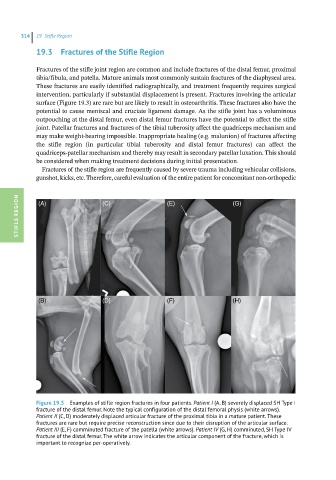

Figure 19.3 Examples of stifle region fractures in four patients. Patient I (A, B) severely displaced SH Type I

fracture of the distal femur. Note the typical configuration of the distal femoral physis (white arrows).

Patient II (C, D) moderately displaced articular fracture of the proximal tibia in a mature patient. These

fractures are rare but require precise reconstruction since due to their disruption of the articular surface.

Patient III (E, F) comminuted fracture of the patella (white arrows). Patient IV (G, H) comminuted, SH Type IV

fracture of the distal femur. The white arrow indicates the articular component of the fracture, which is

important to recognize per-operatively.